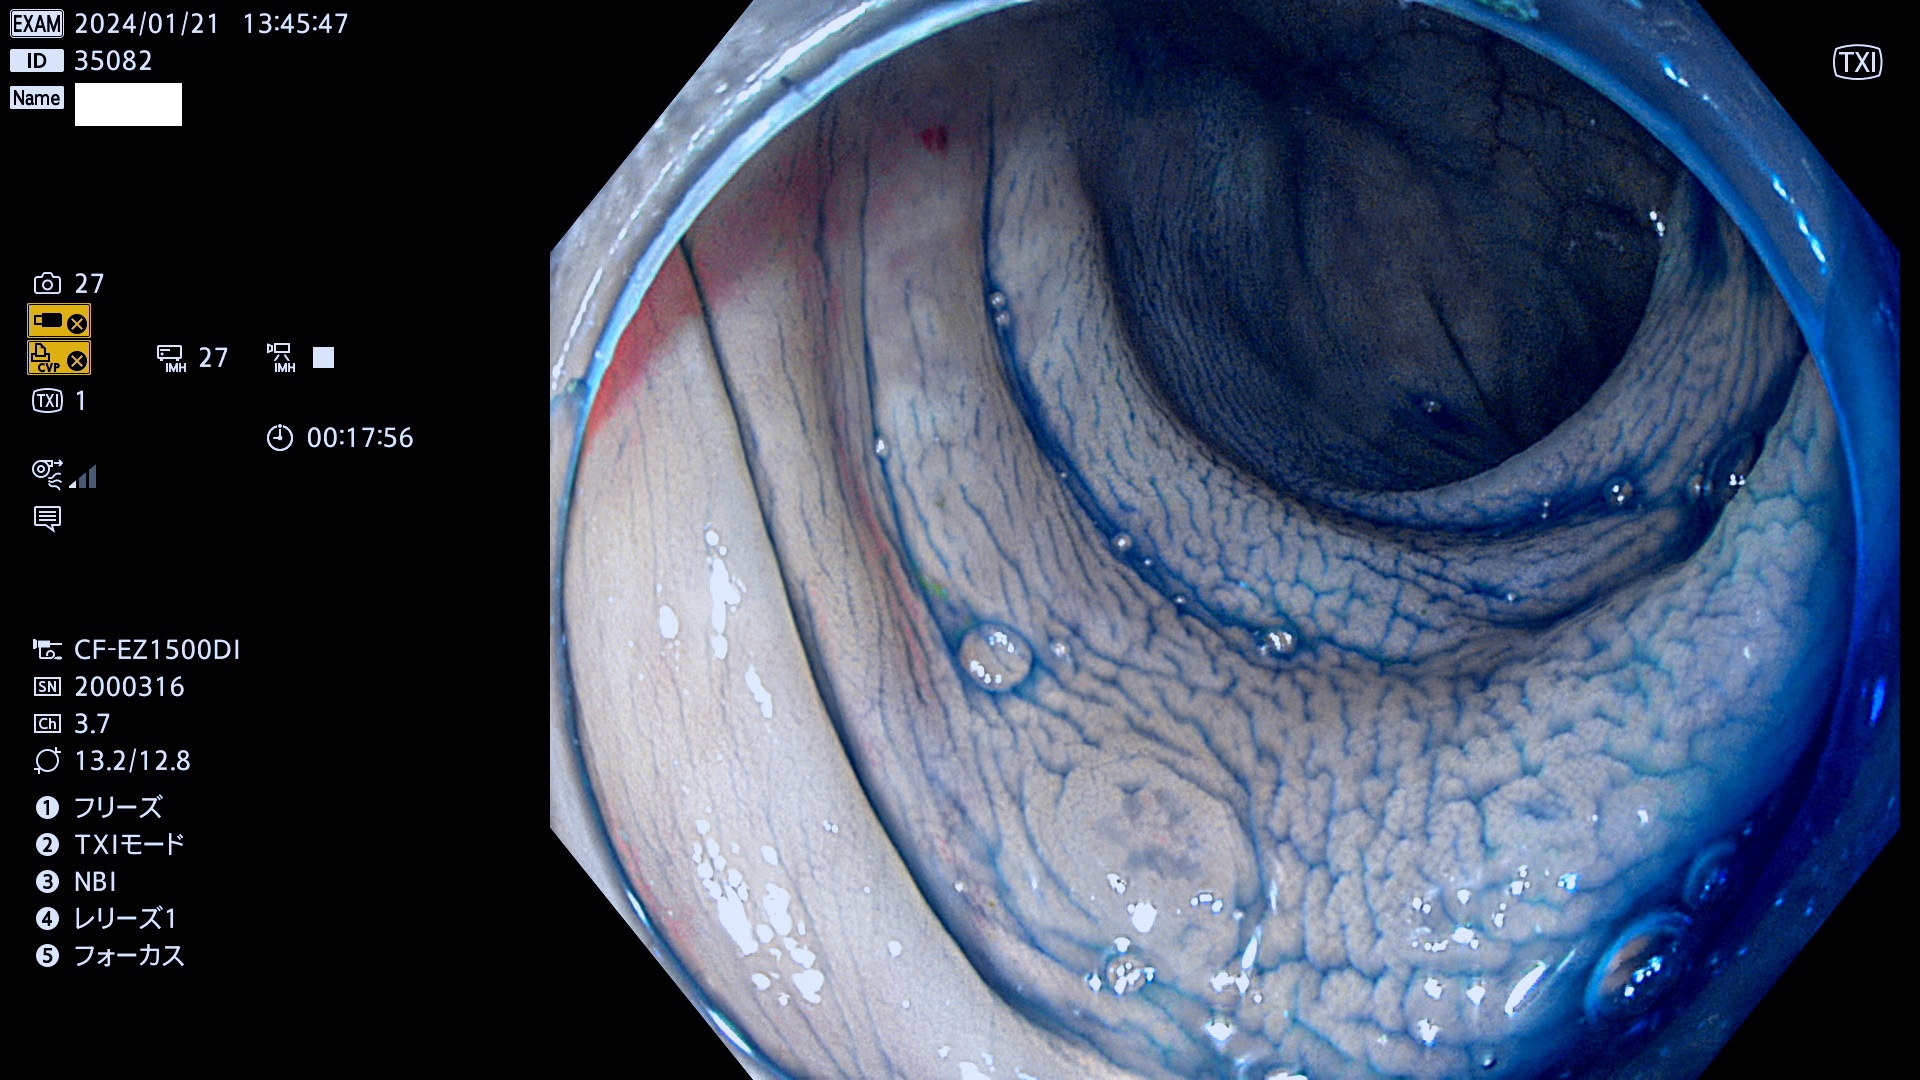

表面型腺腫(Flat Adenoma)の中で、完全に平坦な物をUb、陥凹している物をUcと呼びます。平坦隆起型(Ua)よりも、発見が難しく危険な病変です。

毎週の検査(木・金・土・日)に発見されたUb、Uc型・腺腫を、その週の日曜の夜にUPし1週間、提示します。

抽出の対象期間 2024年1月18日(木)〜1月22(月)の5日間(50件の検査)7件